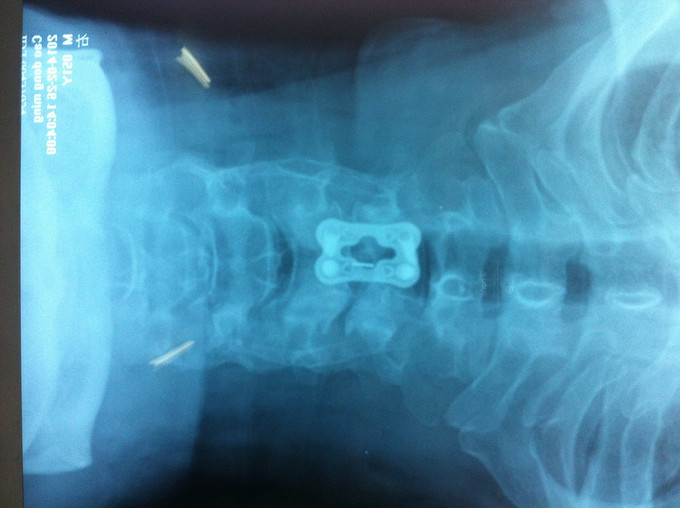

诊断:混合型颈椎病 处理: 1、完善相关辅助检查,明确诊断,有无手术指证; 2、完善手术评估,有无手术禁忌,手术风险及并发症; 3、在全麻下行颈椎前路减压,颈5/6椎间Cage植骨融合内固定术

随访 1、术后患者颈部疼痛较前减轻,双侧上肢疼痛、麻木感觉较前好转,双侧伸肘、伸腕肌肌力4+级。 3、术后1个月,患者上肢麻木明显好转,左侧伸腕、伸肘肌肌力4-5级。 讨论:1、颈椎病手术指证的把握,牵引药物保守治疗与手术减压的选择? 2、颈椎手术前路与后路的手术选择?是否考虑以下问题:1、神经根型与脊髓型;2、是否合并椎管狭窄;3、是单双节段还是多节段间盘突出;4、颈椎前路单间隙还是椎体次全切